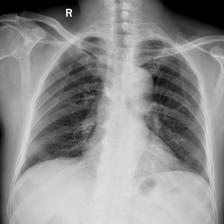

To pre-train a high-performance X-ray foundation model, the first thing we need to do is the collection of large-scale X-ray images. Therefore, a large-scale and high-resolution dataset that contains X-ray medical images is collected for the pre-training. Some representative samples are visualized in Fig. 3.